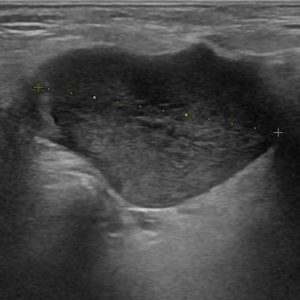

U tuyến nước bọt

Lượt xem: 170» 17-01-2021 -

U tuyến nước bọt

Lượt xem: 174» 17-01-2021 -

U tuyến nước bọt

Lượt xem: 149» 17-01-2021 -

U tuyến nước bọt

Lượt xem: 147» 17-01-2021 -

U tuyến nước bọt

Lượt xem: 146» 17-01-2021 -

U tuyến nước bọt

Lượt xem: 151» 17-01-2021 -

U tuyến nước bọt

Lượt xem: 146» 17-01-2021 -

U tuyến nước bọt

Lượt xem: 136» 17-01-2021 -

U tuyến nước bọt

Lượt xem: 132» 17-01-2021 -

U tuyến nước bọt

Lượt xem: 209» 17-01-2021 -

U tuyến nước bọt

Lượt xem: 150» 17-01-2021 -

U tuyến nước bọt

Lượt xem: 185» 17-01-2021 -

U tuyến nước bọt

Lượt xem: 151» 17-01-2021 -

U tuyến nước bọt

Lượt xem: 212» 17-01-2021 -